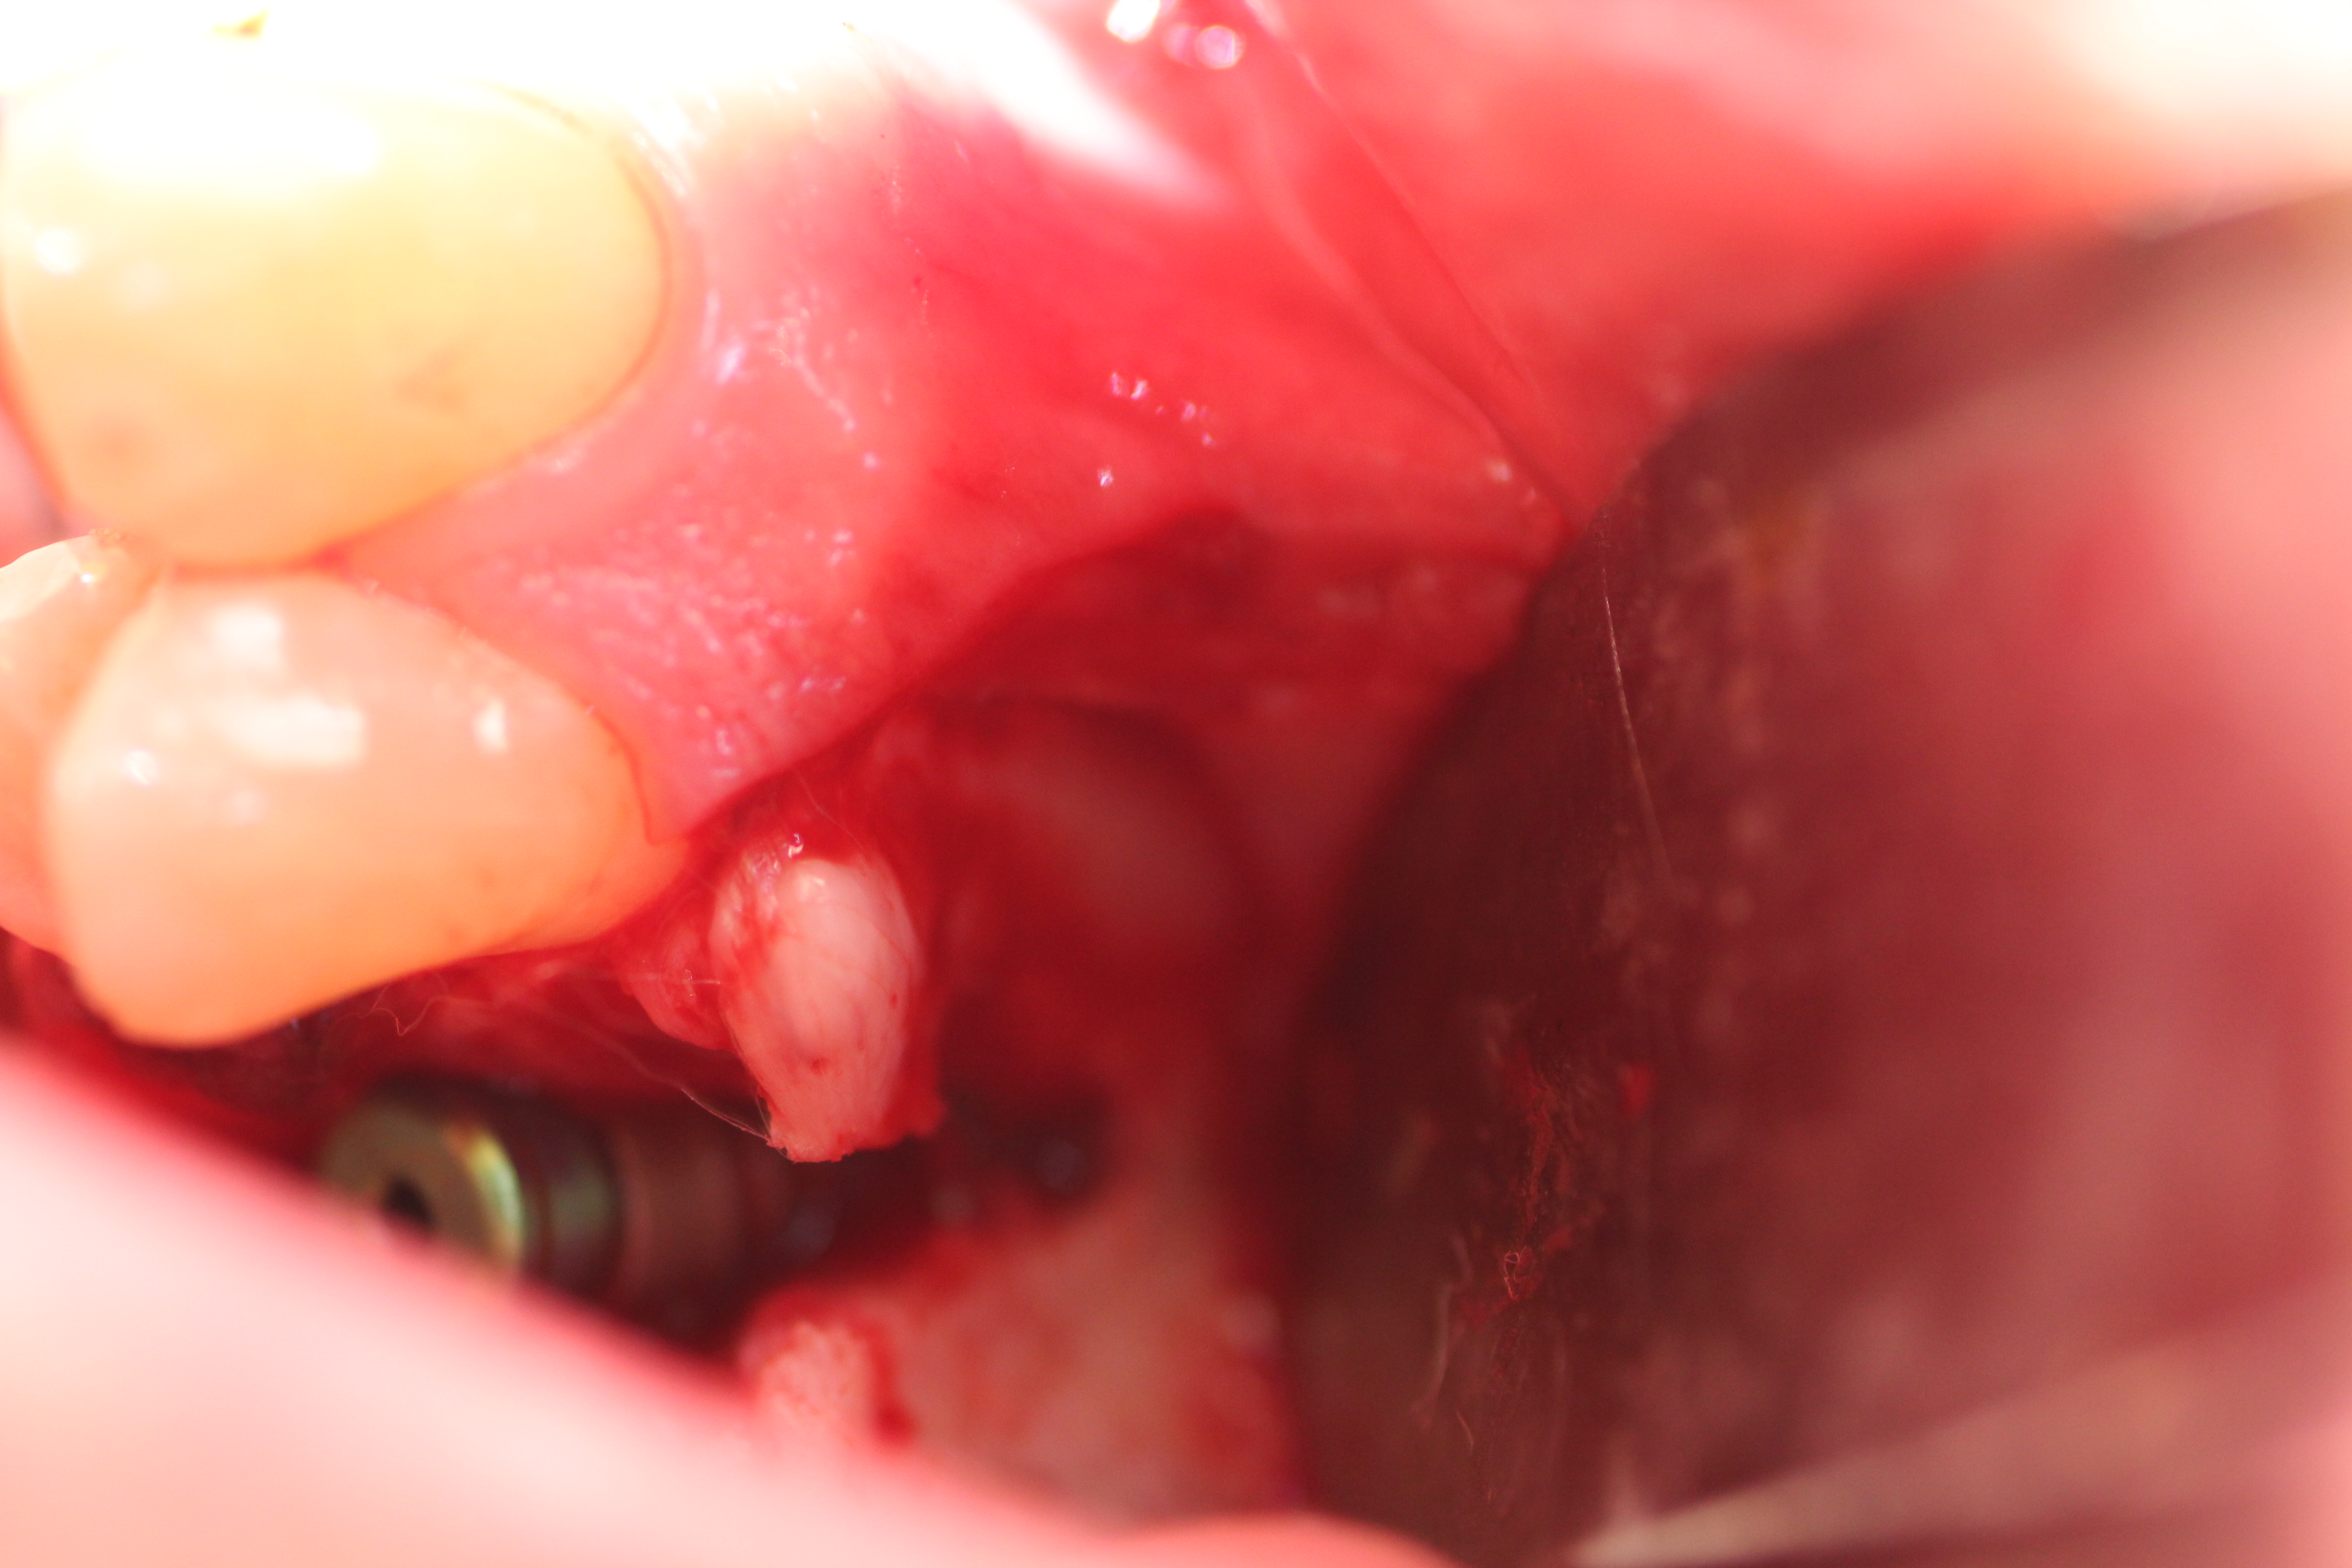

- Implant is in place.

- Bony defect measuring 3mm x 10 mm.

- Human cadaver particulated bonegraft packed into the defect followed by coverage with collagen membrane.